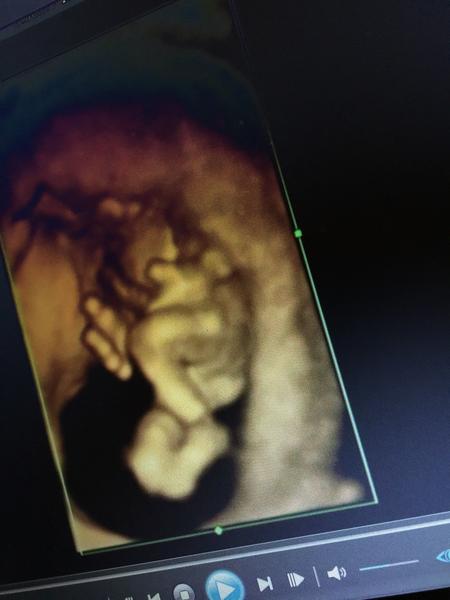

Ahoj maminky a budoucí maminky 😉 Prosím, poradila byste mi některá, co vidíte na fotce z ultrazvuku ve 20. týdnu za pohlaví? Určitě jste foteček viděly už mraky, proto vás žádám o radu...Nechci nikoho ovlivnit, proto svůj tip řeknu později 🙂 Děkuju moc!!!

Myslíte tedy? Mam sice dvě deti,ale jeste ani jednou takto 3D jen u dcerky a to az ve 25 tydnu kdy uz to bylo opravdu videt,ale říka se,že v tom 17-18 tydnu uz by to mělo byt videt 🙂